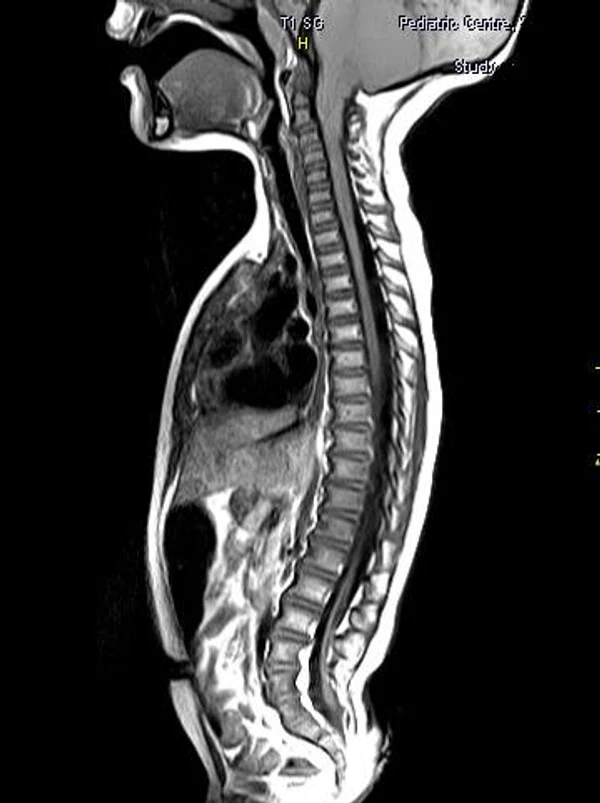

Spina bifida, спинно-мозговые грыжи, диастематомиелия, липоменингомиелолоцеле, фиксированный спинной мозгSpina bifida включают различные типы нарушения закладки и развития нервной трубки на спинальном уровне, что сопровождается незаращением дужек позвоночника и часто сопровождается одновременным пороком развития спинного мозга и его оболочек. Встречаются у 1 на 1000 – 3000 новорожденных. Могут наблюдаться в различных отделах позвоночника, но наиболее часто встречается в пояснично-крестцовом отделе. Незаращение дужек позвонков с наличием грыжевого выпячивания обозначается в литературе по разному: спинно-мозговые грыжи, spina bifida, spina bifida cystica, spina bifida vera, spina bifida typica, spina bifida aperta. Классификация spina bifida aperta: I Рахишизис. II Спинномозговые грыжи. Менингоцеле. Менингорадикулоцеле. Миеломенингоцеле. Миелоцистоцеле. Липоменингомиелоцеле. Основные сопутствующие пороки центральной нервной системы: Гидроцефалия до 65-85%. Аномалия Киари 2. Сирингомиелия.